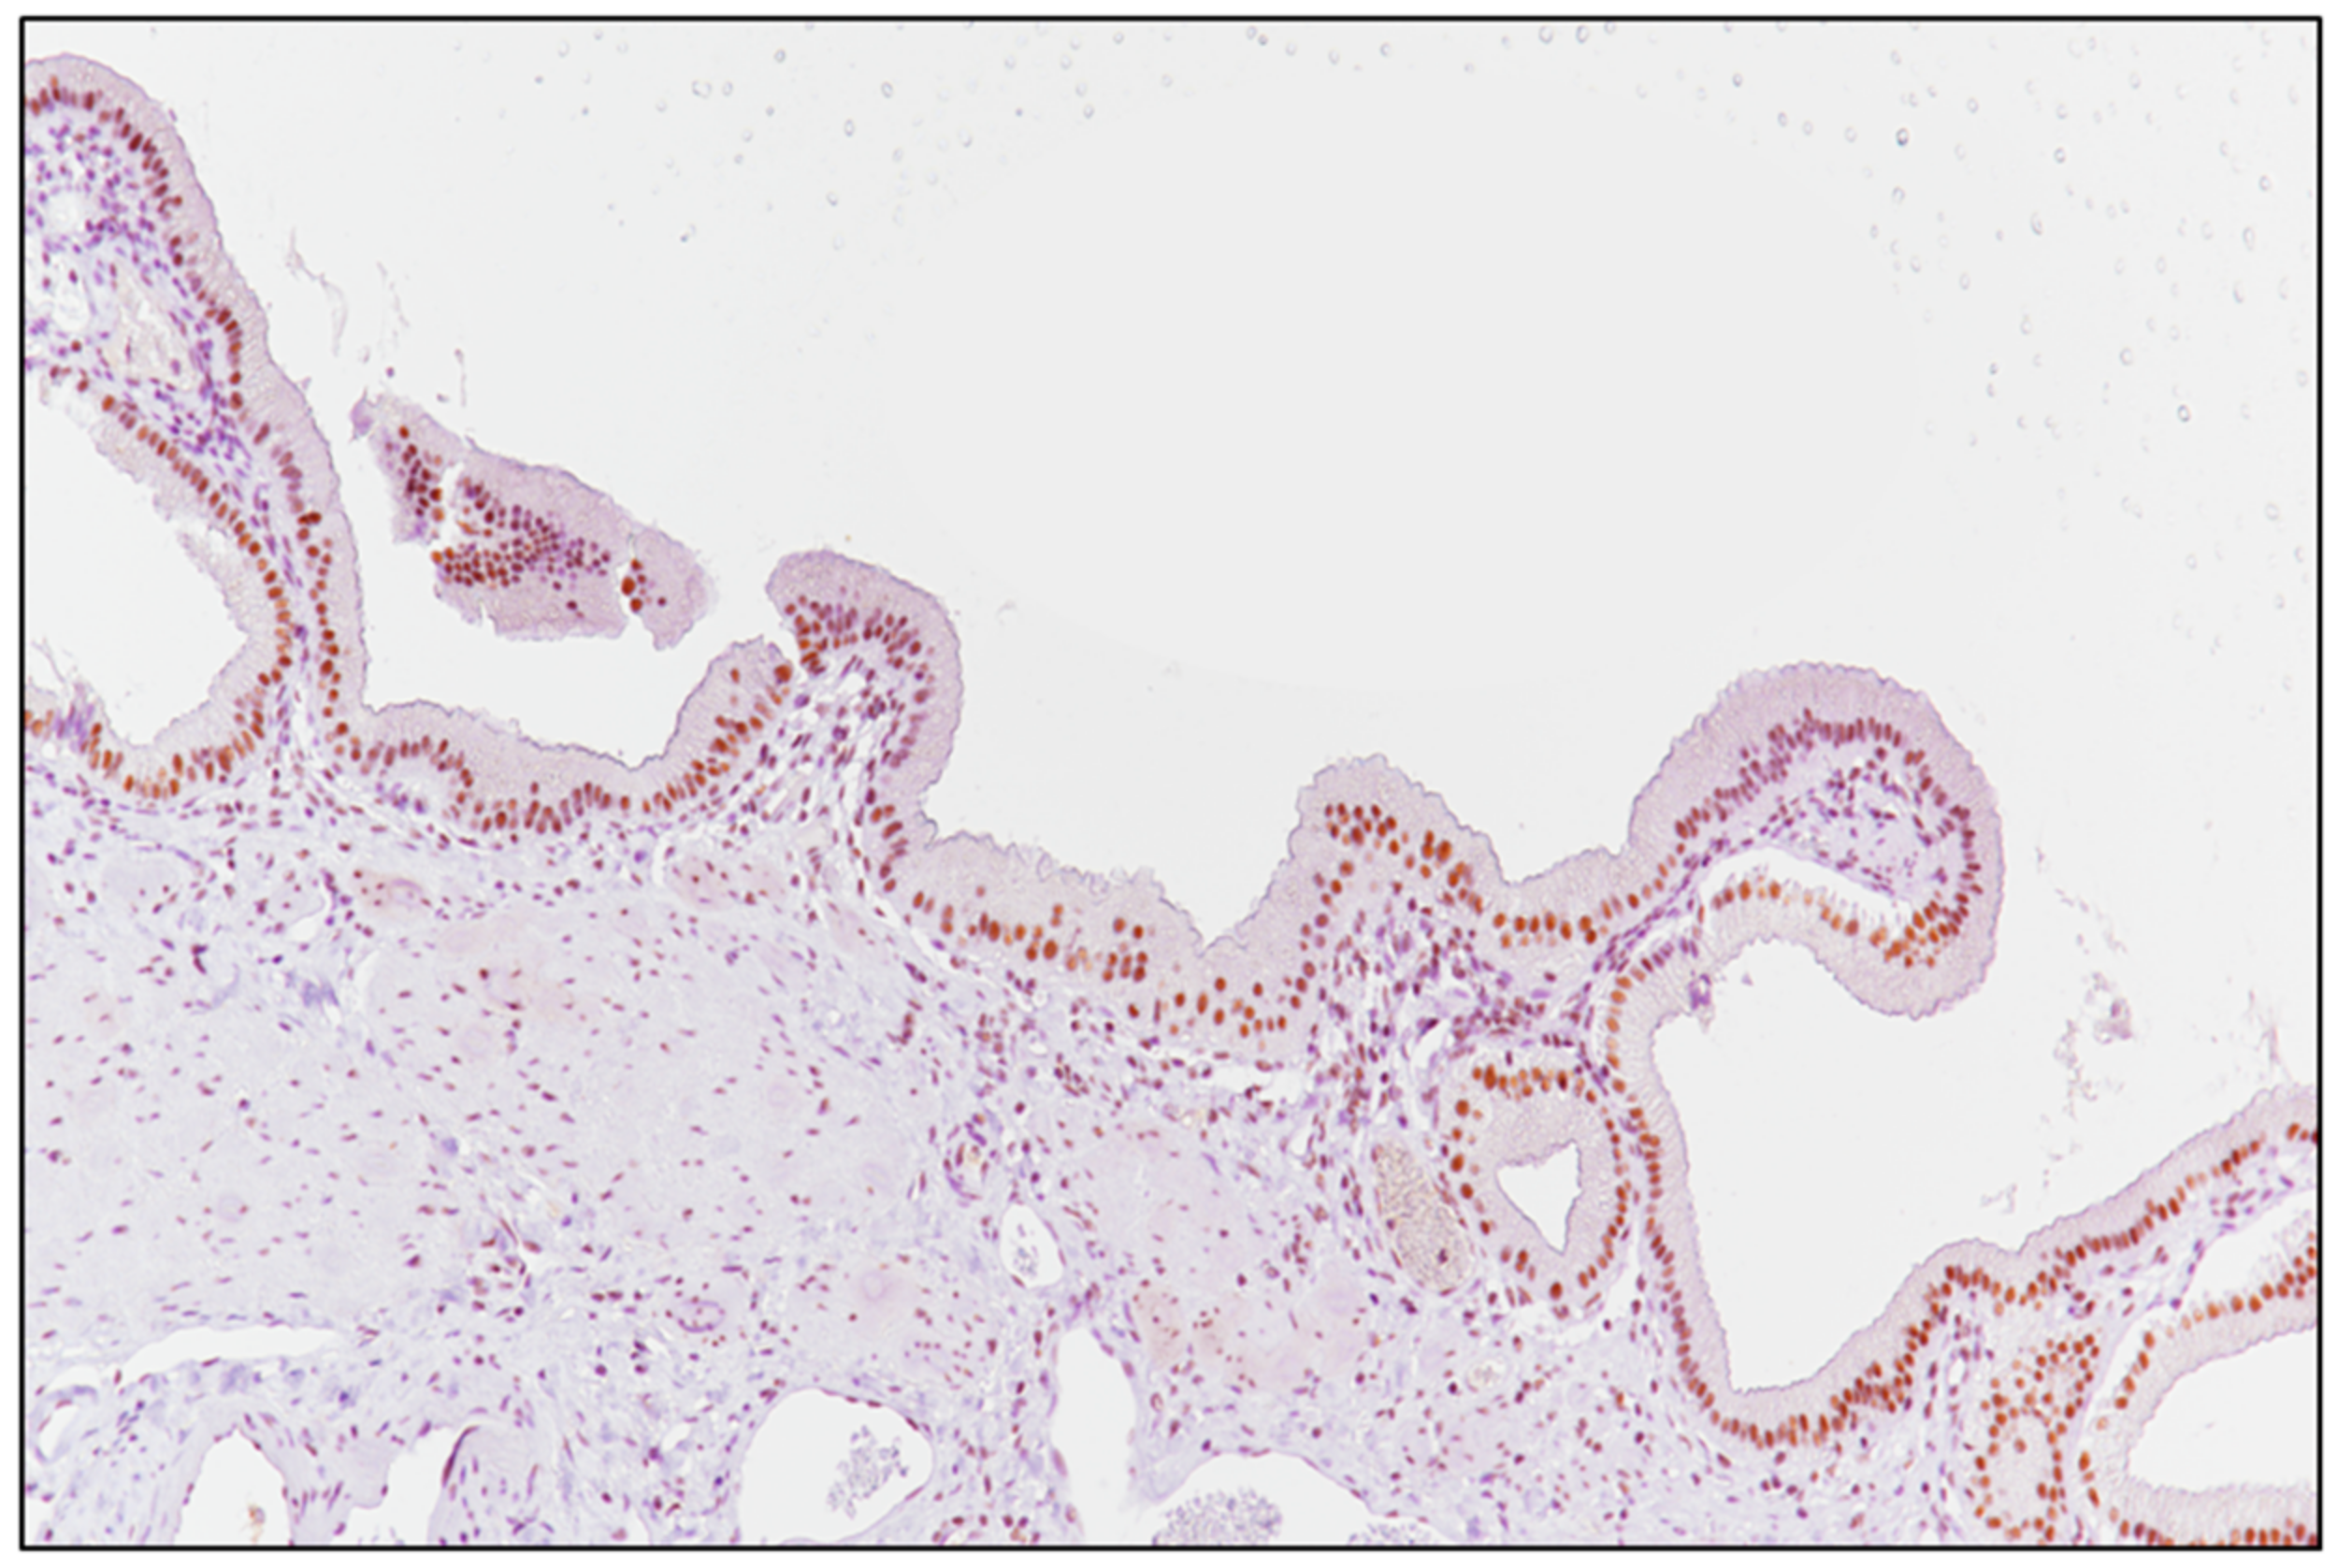

2.2. Laboratory Tests and Evaluation of SRSF1 Immunohistochemistry

3.2. SRSF1 Immunohistochemical Expression and Its Correlation with Prognosis